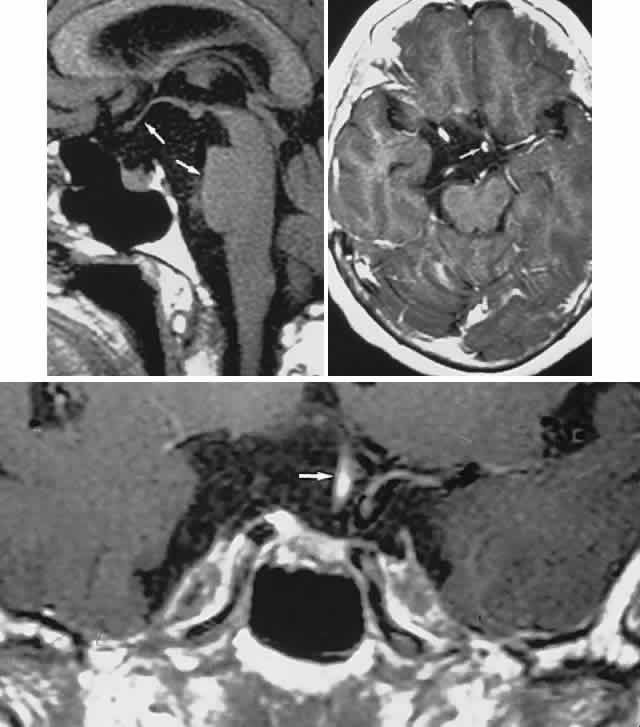

CT scanning retains special relevance to craniopharyngioma diagnosis, currently superior to MRI in detection of calcification and cyst formation (Fig. 7A to C); however, the extent of involvement of adjacent structures, that is, the optic chiasm, third ventricle, and intracavernous carotid artery, is more clearly delineated by MRI (Fig. 7D and E).93 Craniopharyngioma fluid collections are found to be uniformly bright on T2-weighted sequences, but on T1-weighted images, the signal intensity may range from hypointense to hyperintense, reflecting the heterogeneous contents of cysts. Because calcification and cyst formation are hallmarks of craniopharyngiomas, CT is more specific than MRI. At times, intrinsic infiltration of tumor may thicken the chiasm and contiguous optic nerve, a radiologic configuration that mimics glioma.94 Likewise, glioma may be simulated when the optic canal is invaded and enlarged, but accompanying bony erosion of the sella weighs heavily toward craniopharyngioma.

Fig. 7. Computed tomography scan of a large, multicystic craniopharyngioma. A. Axial section through the sella shows destruction of the bony skull base. Axial (B) and coronal (C) sections show cysts (white arrows) and calcification (arrowheads). Contrast-enhanced magnetic resonance imaging of the craniopharyngioma. Sagittal (D) and coronal (E) sections with gadolinium show solid and cystic (arrows) portions.